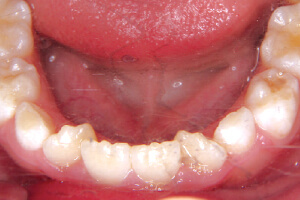

子供の矯正はできる年齢が

限られているのをご存知ですか?

矯正治療の正しい知識がないことで、あとで後悔したくない。そう思う親御様のために、特別な情報をお伝えします。

6歳から8歳で、

下の前歯の生え変わりで

こうなっていれば要注意です。

今現在こうした歯並びになっていると、

将来の歯の並び方は

ガタガタになります。

今すぐのご相談をお勧めします!

6歳~8歳頃、前歯は大人の歯に生え変わってきます。前歯の凸凹やガタガタを綺麗に整えます。